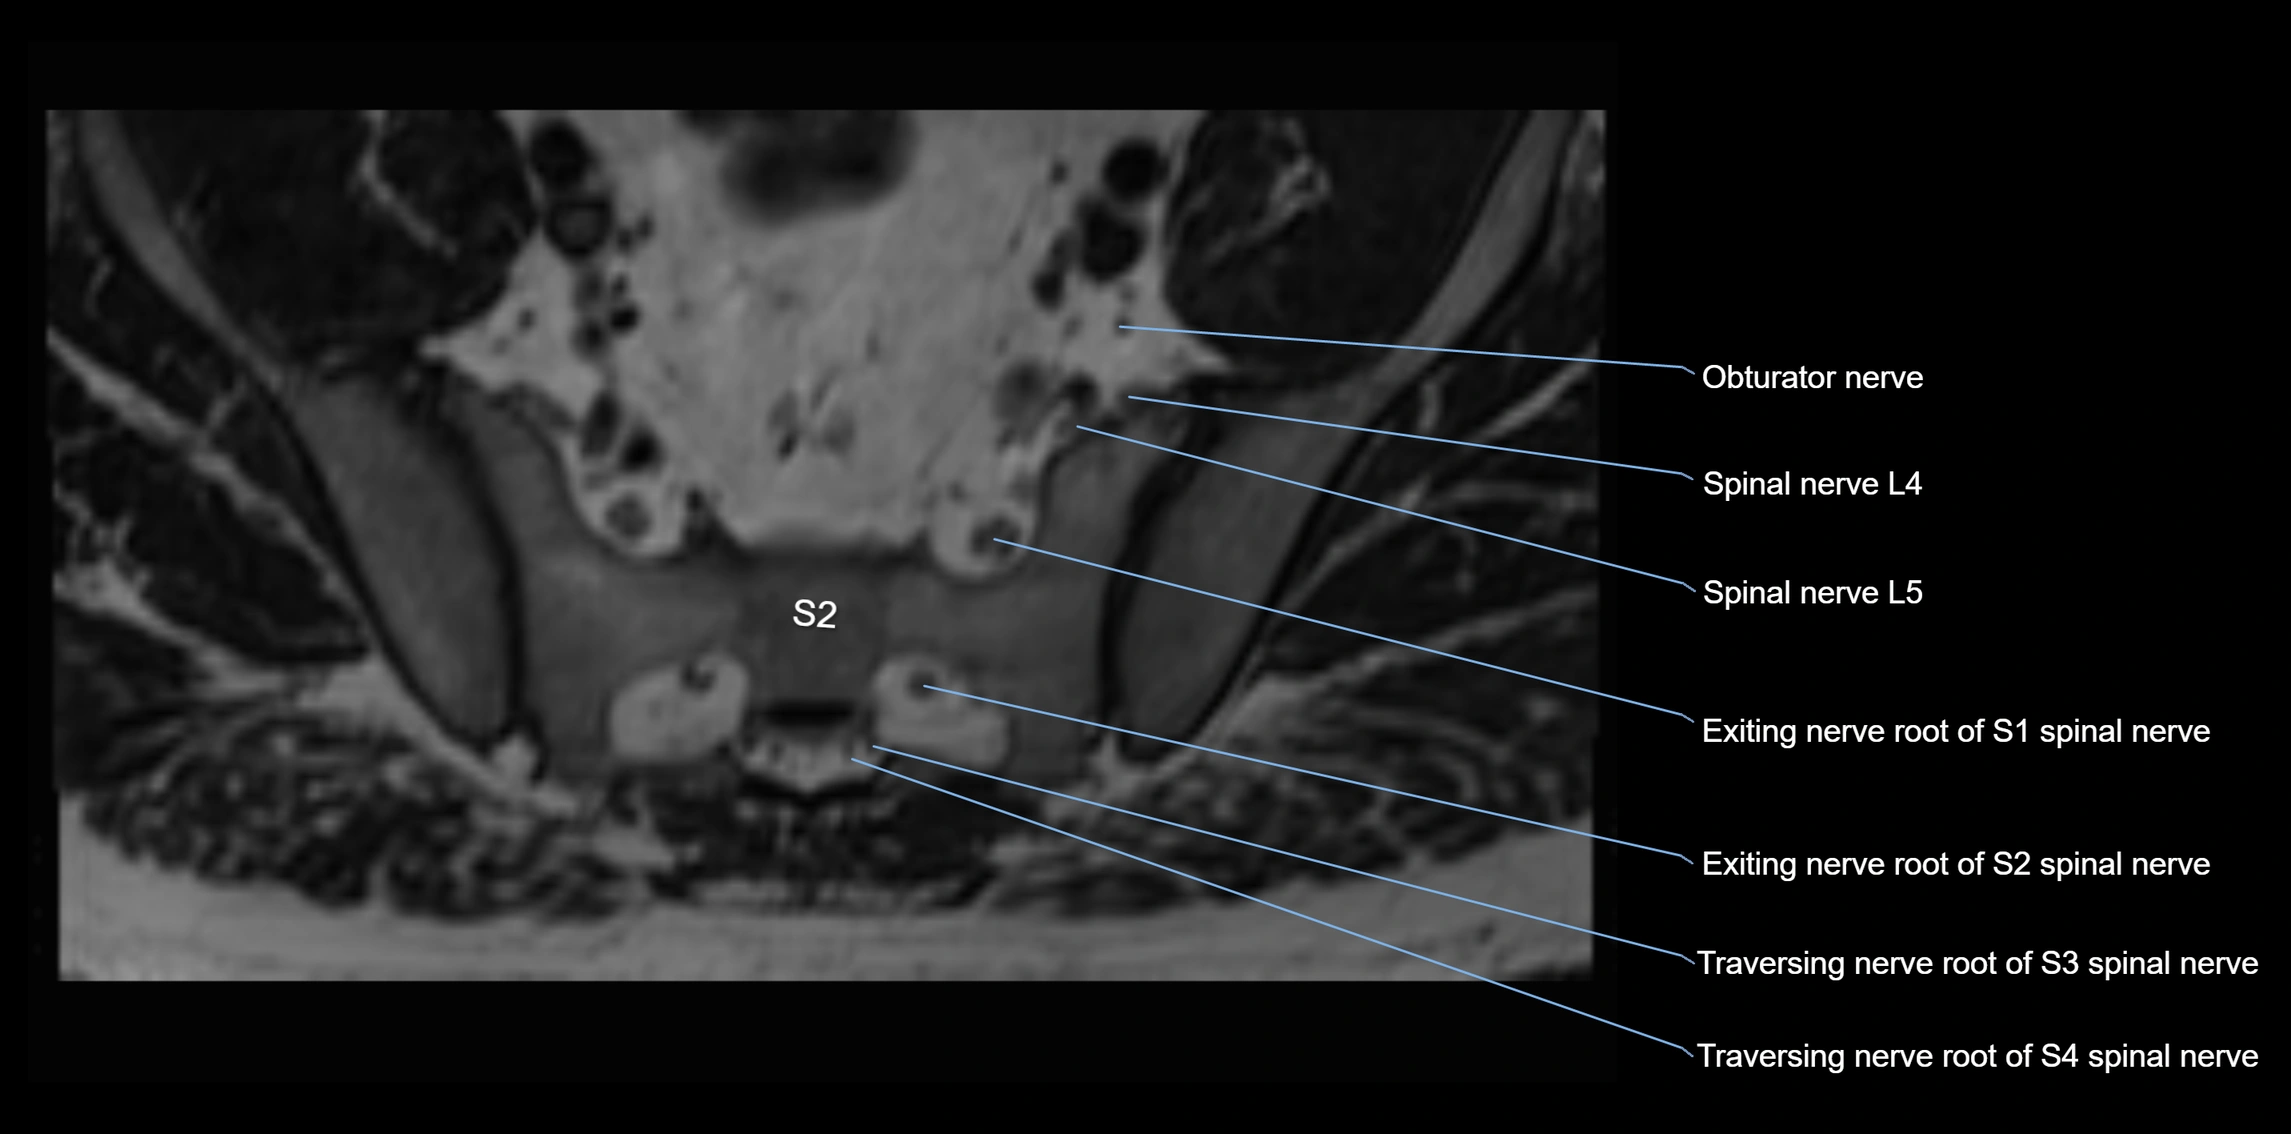

MRI Appearance

T1-weighted images:

• Nerve appears as a very thin low-to-intermediate signal intensity structure

• Surrounded by bright fat, aiding visualization

T2-weighted images:

• Nerve shows intermediate to mildly hyperintense signal compared to muscle

• Pathological involvement appears brighter

STIR (Short Tau Inversion Recovery):

• Normal nerve appears dark

• Inflamed or entrapped nerve appears bright hyperintense

T1 Fat-Sat Post-Contrast:

• Normal nerve enhances minimally

• Pathologic nerve (neuritis, entrapment, tumor infiltration) shows focal or diffuse enhancement

3D T2 SPACE / CISS:

• Nerve appears intermediate to mildly hyperintense compared to muscle

• Surrounded by bright fat or CSF, improving visualization

• Best sequence for mapping small pelvic nerves such as the anococcygeal

MRI image

image